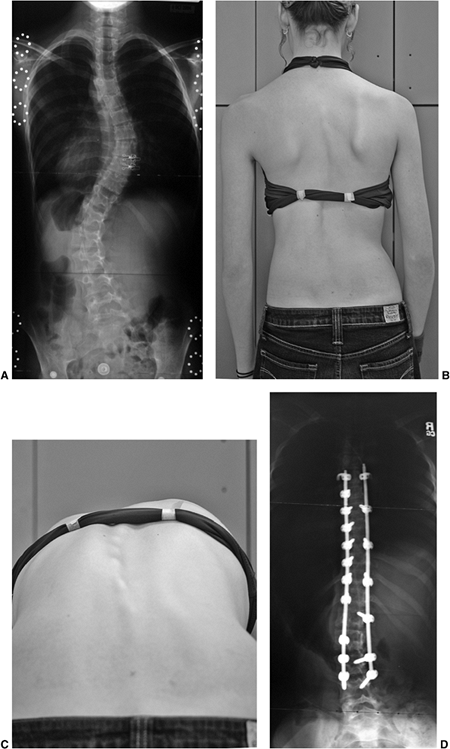

![]()  |

Figure 18.9 A: A 28-degree right thoracic scoliosis as seen on the posteroanterior radiograph. B:

The Adams forward bend test demonstrated an 11-degree scoliometer measurement, indicating a corresponding measure for the angle of trunk rotation associated with this scoliosis. The forward bend test remains one of the most reliable means of detecting early scoliosis, other than a radiograph. Scoliometer measurements greater than 7 degrees generally warrant a screening posteroanterior radiograph.  |